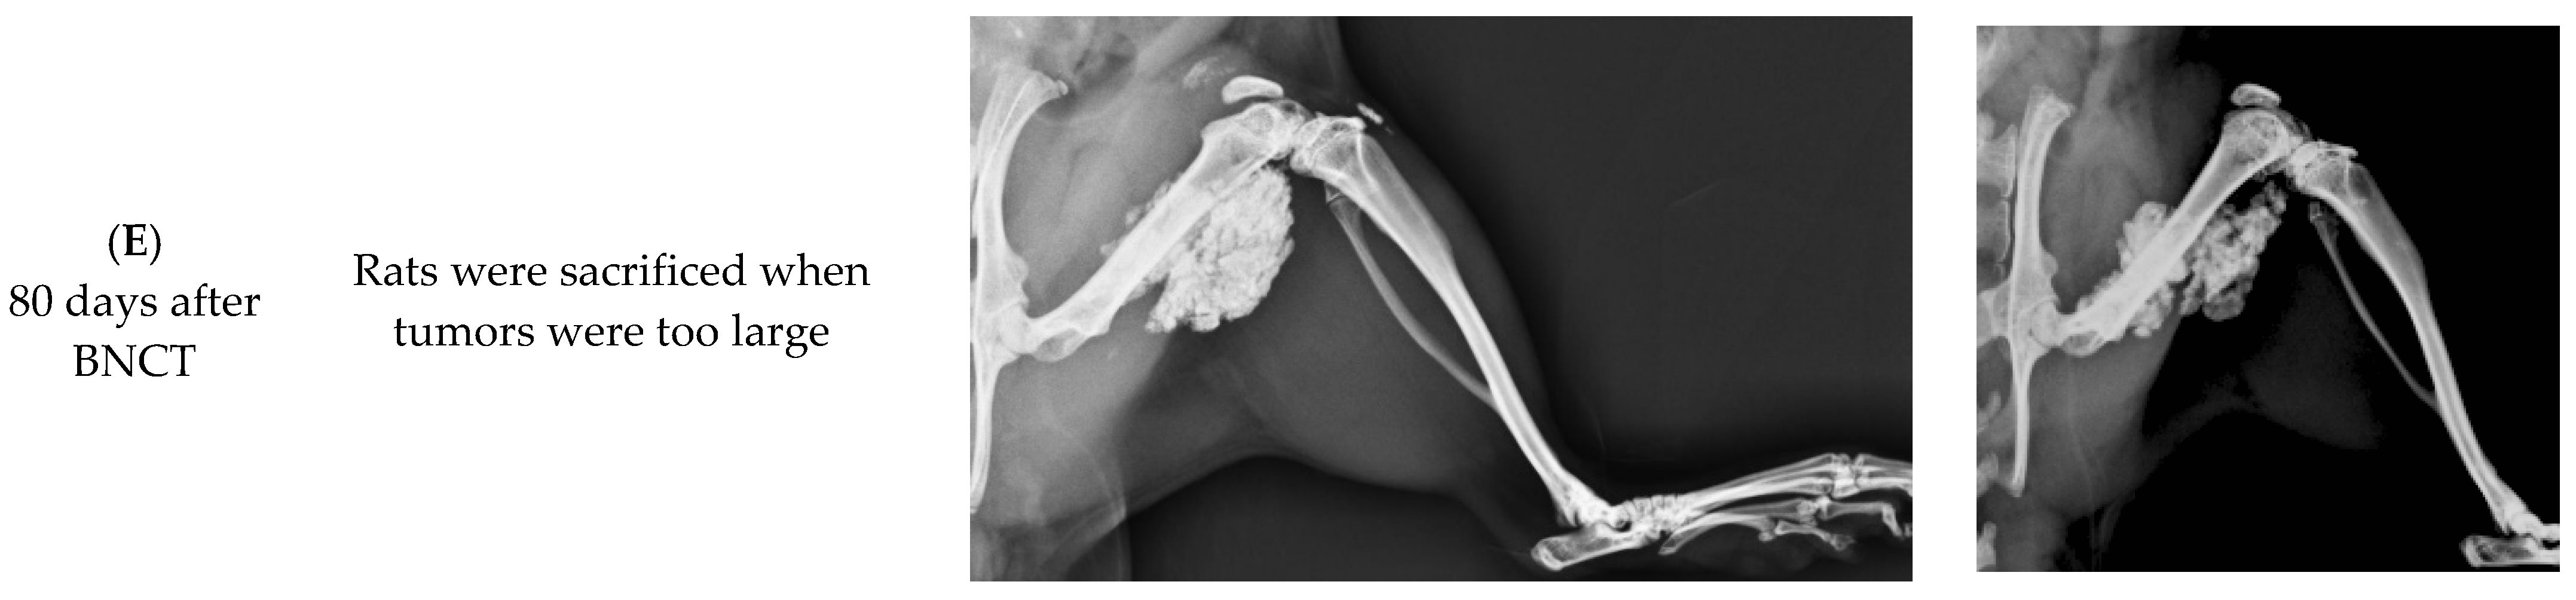

3.4.2. Radiographic Investigation

Radiographs of the hind limbs of rats were obtained. Figure 4 displays the radiographs of the tumor control, high-dose-treated and low-dose-treated rats on the day before BNCT and 10, 30, 60, and 80 days following BNCT treatment. The reductions of the tumor sizes in the BNCT-treated groups were investigated, and increases in tumor sizes in the tumor control group were observed. The tumor sizes declined significantly on the 30th day following BNCT. Inhibition of tumor growth and tumor shrinkage were apparent when tumor cells were injured as a result of BNCT. By day 80 after BNCT, high-radiodensity scar tissue had been formed by the shrinkage of the large tumors in both high-dose and low-dose BNCT groups. Evidently, BA-mediated BNCT significantly and rapidly shrank the extraskeletal tumor.

Figure 4.

Radiographic investigation of BA-mediated BNCT rats. Radiographs taken of rats in the high-dose BNCT group and the low-dose BNCT group were obtained on the day before BNCT and the 10th, 30th, 60th, and 80th days after BNCT, respectively. The OS-bearing rats in the tumor control group were sacrificed and data were collected until day 30.

On the 10th day following BNCT, a small radiolucent lesion was present on the posterior site of the injection in the tumor control group. On day 30 after BNCT, the radiolucent lesion was shown on the posterior site of the injection, and the radiolucent lesion on the anterior site of injection was also increased. The progressive radiolucent lesion was extending in the tumor control group and the rat was sacrificed when the tumor was too large.

In this study, the UMR-106 cell suspension was injected into the parosteal muscles and distal femoral epiphysis or metaphysis. Thus, OS formed in the distal femur and extraskeletal tumors in the parosteal muscles. These tumor models were used to study the therapeutic and radiobiological effects of boric-acid-mediated BNCT. BA-mediated BNCT was verified to have the potential of treating OS of the femur, by shrinking the tumor and healing the bone. BA selectively accumulates in OS tissue, and is involved in tissue calcification during the development of OS. The rapidly grown Os produced more osteoid in tissues, causing the accumulation of more BA in the tumor tissue. However, as shown in Figure 4, the low-dose BNCT group does not appear to be significantly different from the high-dose BNCT group, possibly indicating that low-dose BNCT has sufficient therapeutic effect on OS. The clinical relevance of each entity requires further study.